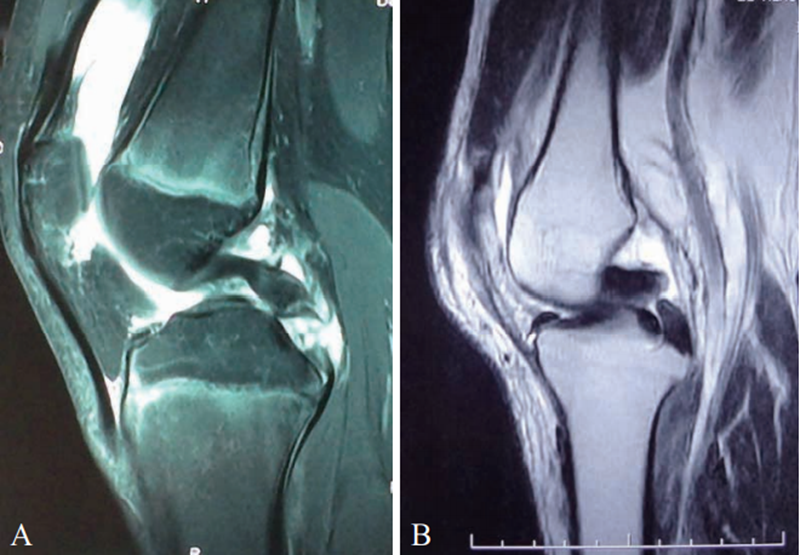

图10 PCL损伤MRI影像

A. 12岁患者脂肪抑制像显示PCL从邻近胫骨止点部位断裂;B. T2像显示PCL从纤维中部断裂

MRI检查对于急性PCL损伤准确率可高达100%,对于慢性PCL损伤虽然准确率高但敏感度差。PCL信号改变、增粗、断裂、迂曲或消失等均为损伤信号(图10)。